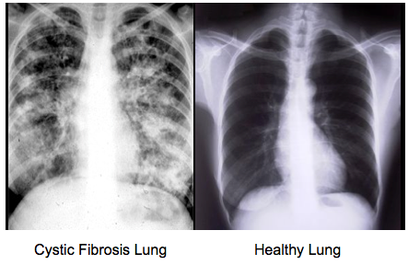

Cystic fibrosis lungs on the left and healthy lungs on the right

One year of gene therapy treatment for cystic fibrosis resulted in 3.7% improvement and stabilization of the disease compared to a placebo group. Cystic fibrosis affects about 70,000 people worldwide. Mutations in a single gene – CFTR – cause problems around the body, but particularly in the lungs. People with cystic fibrosis produce thick, sticky mucus, which clogs up the organ and makes it a breeding ground for harmful bacteria.